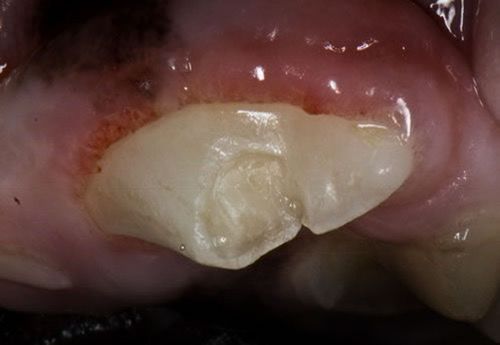

Bonded Sealants

✔  Learn when bonded sealants are appropriate in your dental program ✔  Understand how to apply bonded sealants correctly ✔  Avoid mistakes that can cause harm or ineffective treatment ✔  Discover the products and equipment needed for proper application ✔  Receive a printable checklist of all required items